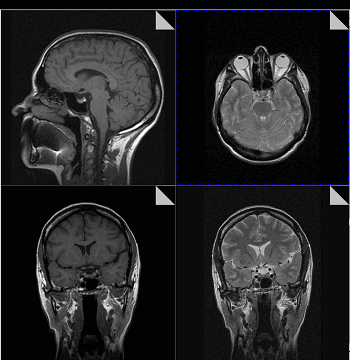

- Томография. Для определения стадии заболевания и получения более полных данных о структуре, размере и расположении фибросаркомы при необходимости назначают КТ и МРТ.

Магнитно-резонансная томография или МРТ - это сфокусированный метод, который проводит очень детальное обследование. Диагностическая точность МРТ превышает УЗИ и во многих случаях КТ, за исключением сканирования полых органов (легких, желудка, кишечника) и костей. МРТ является золотым стандартом диагностики:

- заболеваний головного и спинного мозга;

Принцип работы МРТ основан на эффекте ядерного магнитного резонанса. МР томограф в своей конструкции имеет мощный магнит, который создает магнитное поле, и датчик, который подает радиочастотные сигналы. В такой ситуации протоны атомов водорода начинают колебательные движения, выделяя при этом импульсы. Их улавливает компьютер томографа и преобразовывает в трехмерные изображения. Чем больше воды содержится в клетках ткани, тем детальней получается ее изображение. Поэтому на МРТ хорошо отображаются органы с большим содержанием воды: МРТ головного мозга, МРТ спинного мозга, МРТ глазных орбит, МРТ органов малого таза, МРТ позвоночника, МРТ суставов, и плохо визуализируются органы с большим содержанием воздуха МРТ органов грудной клетки или кости.

МРТ будет эффективно при исследовании опухолей, мозга и аномалиях развития сосудов.

Магнитно-резонансная томография

В основе МРТ лежит явление магнитного резонанса, основанного на переизлучении радиоволн, взаимодействующих с атомами водорода, в избытке содержащимися в организме человека. Эти переизлученные электромагнитные волны улавливаются датчиком МР-томографа, усиливаются и в виде цифровых изображений появляются на экране монитора. Это безвредный и абсолютно безопасный для здоровья человека метод лучевой диагностики, так как в основе получения изображения отсутствует рентгеновское излучение, поэтому МРТ можно проходить неограниченное количество раз, с любым интервалом.

Существенное преимущество МР-томографии перед КТ заключается в том, что она не противопоказана беременным во II и III триместре и совершенно безопасна для детей. В МРТ исследуемая область сканируется в трех проекциях, что позволяет врачу-рентгенологу в полной мере оценить состояние тканей и органов исследуемой области, а высокая контрастность изображения и пространственное разрешение позволяют визуализировать серое и белое вещество головного мозга, оценивать состояние костного мозга и мягких тканей различной локализации. Кроме того, метод МРТ позволяет получать изображения сосудов головного мозга и сосудов шеи без введения контрастного препарата.

Мы также всегда делаем КТ пациентам с подозрением на нарушение мозгового кровообращения, исследование позволяет не только подтвердить диагноз, но и оценить «масштаб» поражения и выработать верную тактику. Назначают его при патологии почек, в частности, при наличии камней. На томографе можно увидеть их расположение, оценить плотность и структуру, а значит, принять решение об операции или выборе консервативных методов. МРТ имеет преимущества при изучении патологий суставов, для диагностики заболеваний головного мозга, спинного мозга, органов малого таза.